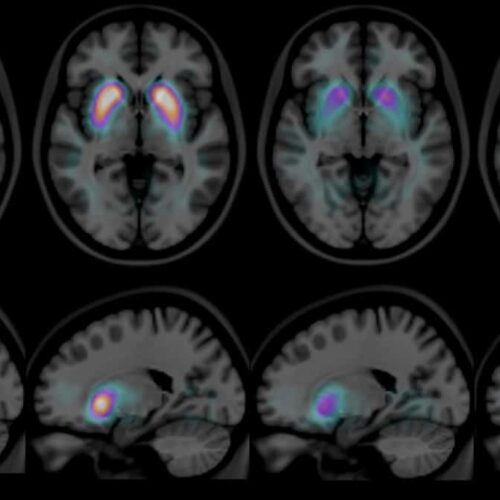

Kann Demenz geheilt werden?

Demenz ist keine einzelne Erkrankung. Kognitive Beeinträchtigungen können bei manchen Ursachen reversibel sein. Beispiele:...

Was bedeutet Pseudotumor cerebri?

Es liegen Zeichen eines erhöhten Hirndrucks vor, ohne dass ein Hirntumor besteht. Der Liquor ist meist unauffällig, und eine klare Ursache...